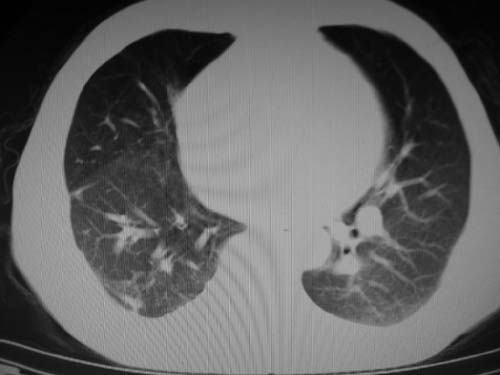

男,80岁

肺a高压征[左肺a狭窄?];肺,胸膜tb

右肺上叶结核;左肺门占位?建议增强扫描.

左下肺静脉扩张,原因?建议cta

左肺动脉异常增粗,建议增强。

1)考虑肺动脉狭窄。2)右肺上叶继发性肺结核。3)右侧胸膜增厚、钙化,左侧胸膜反应。

肺动脉瘤。建议先行ct增强扫描

左肺动脉异常增粗,考虑肺动脉狭窄可能。

右肺上叶继发性肺结核。

右侧胸膜增厚、钙化,左侧胸膜反应。

左肺动脉异常增粗,建议ct增强,排除肺门肿瘤

右侧胸膜增厚、钙化,左侧胸膜反应

1)考虑左肺动脉瘤可能性大,建议增强。2)右肺上叶继发性肺结核。3)右侧胸膜增厚、钙化,左侧胸膜反应。

肺动脉段突出,左右肺门不等大,左肺门明显增大,肺动脉干及左肺动脉明显增宽,考虑先天性肺动脉狭窄瓣膜狭窄型。

)考虑肺动脉扩张,右心室增大,主动脉弓段正常位弓后段明显变小(不会是动脉导客未闭吧,不知患者有何症状病史)0。2)右肺上叶继发性肺结核。3)右侧胸膜增厚、钙化,左侧胸膜反应。

右肺上叶尖段结核;左肺下叶占位?建议增强扫描。右侧胸膜增厚;右肺局限性肺气肿。

肺动脉高压,左肺动脉瘤样扩张。